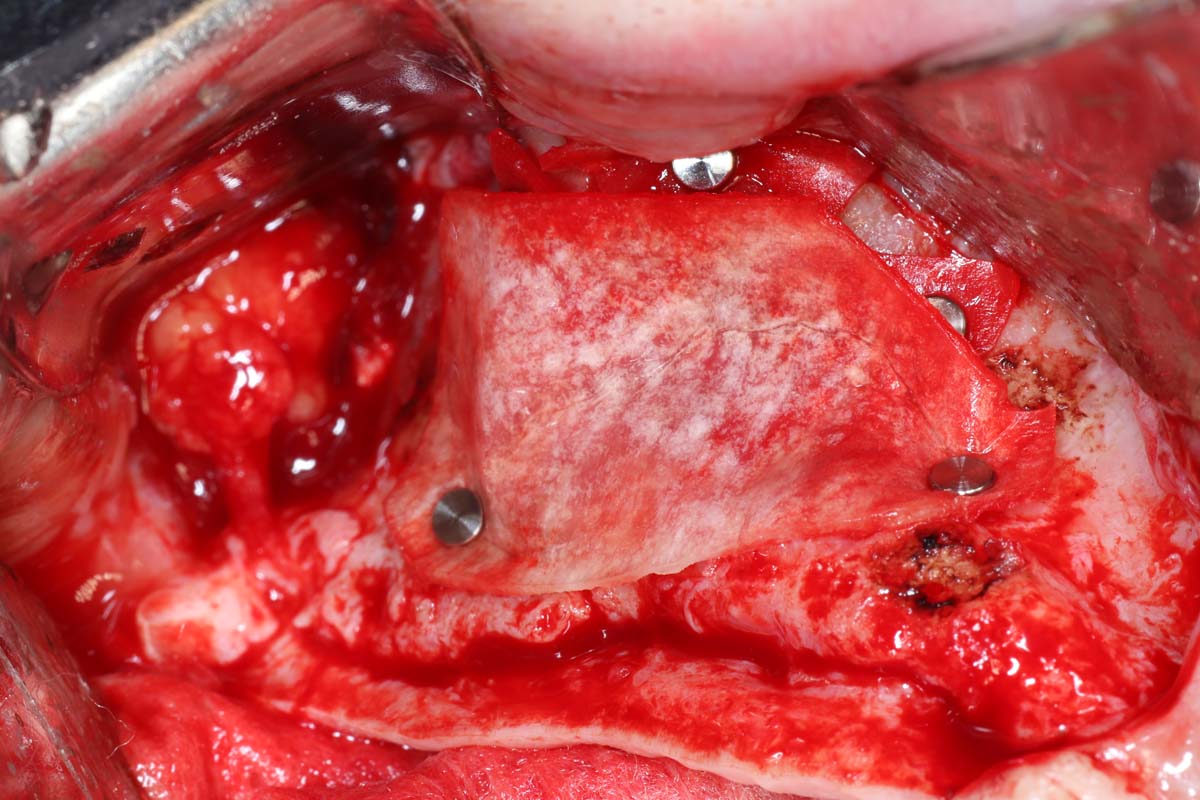

Learn from Dr. Pikos' 1,600+ Sinus Grafts

Gain insights from Dr. Pikos' extensive experience with over 1,600 sinus grafts. Discover successful techniques, common pitfalls, and nuances of grafting materials. Tackle complex cases and implement tips to ensure stability and integration for effective sinus augmentation outcomes.

Gain Hands-On Skills and Watch Live Surgery to Master Implant Site Development Techniques

Elevate your skills in implant site development with hands-on practice and live surgical demonstrations. Observe procedures in real time and participate in practical sessions to build confidence in essential techniques, from bone grafting to soft tissue management.

- Indications and step by step surgical protocol for sinus bone grafting – lateral and crestal approach.